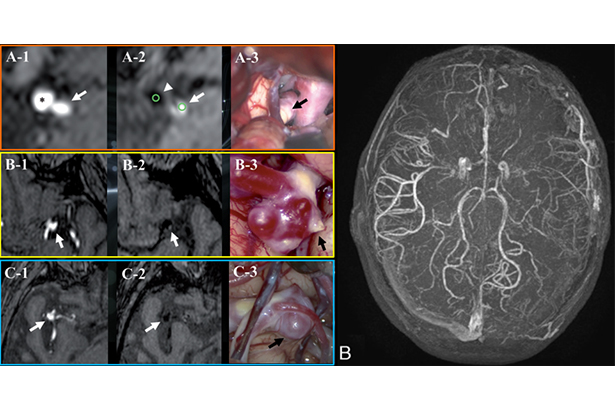

高分辨HOP MRA成像同時使用亮血和黑血兩種血管成像技術,一次掃描獲得三組圖像(TOF、FSBB、HOP),可以進行管腔狹窄評估,得到遠端血管信息 ,同時實現血管壁斑塊成像。

FSBB/eFSBB佳能新一代佳能磁敏感技術,200um超高分辨力,可精細顯示顱腦微血管如丘腦豆紋動脈。